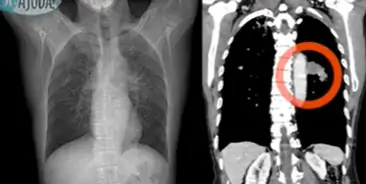

O diagnóstico inicial costuma ser feito por meio de exames como raio-X do tórax ou tomografia. Na presença de nodulações ou imagens suspeitas, a investigação é complementada com uma biópsia, procedimento que retira uma amostra da área suspeita para análise laboratorial.